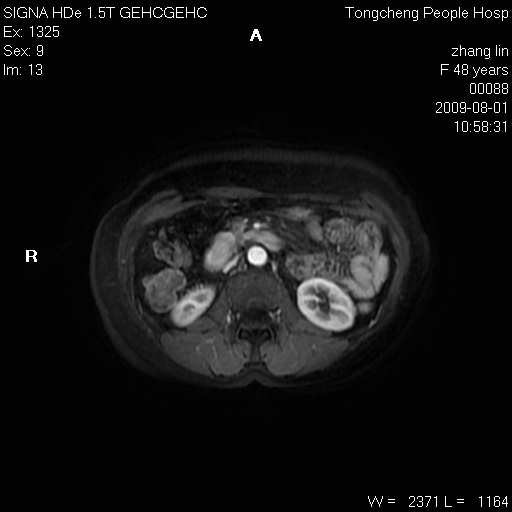

女,48岁。健康体检,彩超发现右肾占位性病变。平素健康。

临床诊断:右肾占位性病变,性质待定(囊肿?肿瘤?)。

上中腹部mr平扫+增强扫描,图像如下:

右肾上极见一类圆形病灶,t1wi呈等信号t2wi呈等高混杂信号,三期增强无强化,边界清---考虑囊肿出血。

同反相位均表现为等信号,病变无强化,考虑含蛋白的囊肿可能,弥散加权相或许有些帮助,